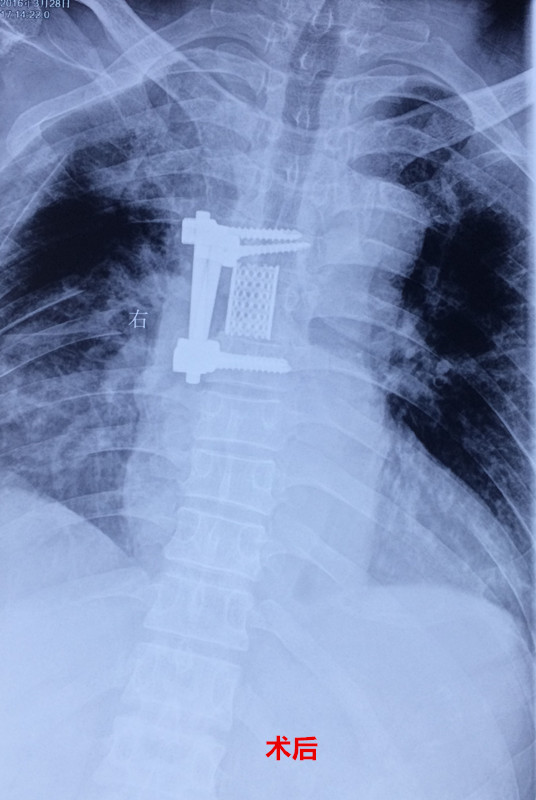

患者入院后,王栋副主任,李锋涛主治医师高度重视,仔细询问患者病情,进行专科查体,分析以往患者的影像学资料,由于肿瘤组织生长巨大,严重压迫右肺,并且已经破坏了胸6椎体及其附件、右侧第6肋骨等,局部结构复杂,为了帮助手术方案的设计,我们采用3D打印技术,术前将肿瘤局部解剖结构打印成3D模型。邀请胸外科张维教授多次会诊,根据3D打印模型制定了详细的手术计划及围手术期治疗方案。经过严密的手术前准备,以王栋副主任、张维教授为主刀、李锋涛主治医师为助手,吴刚副主任医师、罗斌医师为麻醉医师,殷敏、马霞为配合护士,黄亚娟、王芳医师为术中诱发电位监护医师的手术团队努力下,手术顺利完成,成功切除了胸腔内、椎体旁及椎管内肿瘤组织,并进行了脊柱的重建。术后患者恢复良好,很快下肢感觉、肌力恢复,现患者正在康复中。

由于脊柱具有特殊的解剖结构,前方紧邻大血管及内脏,两侧有神经根走行,椎管内是脊髓,这就使得脊柱肿瘤的完整切除变得十分复杂,并且脊柱肿瘤复发后再次手术切除的机会很小,因此脊柱肿瘤手术难度大,复发率高,疗效差,一直是骨肿瘤治疗中的难点。近年来,骨二科先后开展了各种类型的原发性及转移性脊柱肿瘤的手术治疗,尤其是对于单个椎体肿瘤的整体切除,明显减少了术后的复发率,提高了患者的生存时间。对于复杂的脊柱肿瘤,由于局部解剖结构紊乱,使得手术切除变得十分困难,因此我们结合最新的3D打印技术,在术前诊断肿瘤局部进行3D打印,制成模型,在术前根据具体模型设计最佳手术方案及切除范围,术中参考3D模型提高具体操作效率,避免血管神经损伤,明显减少了手术时间及术后并发症,获得了良好的治疗效果。